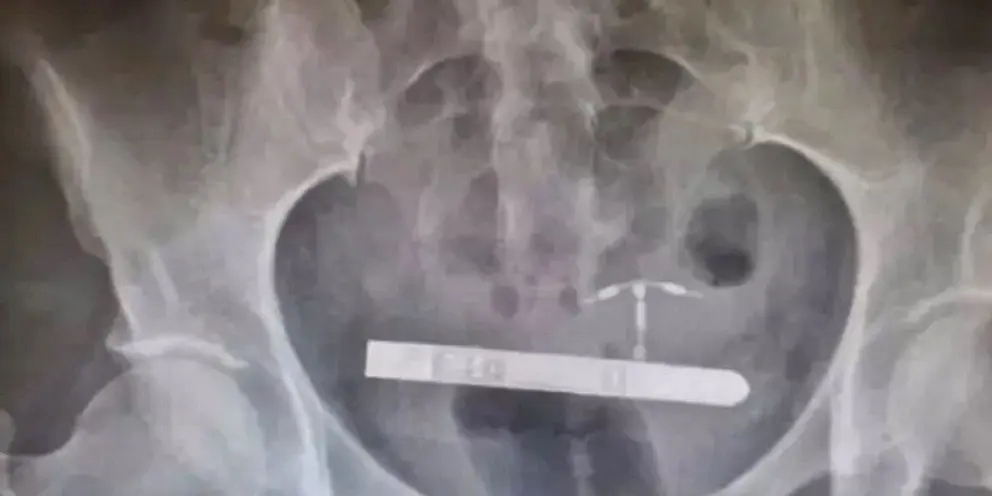

“El personal de la sala de emergencias no fue capaz de encontrarlo en la vagina”, explica el doctor Greg Marchand, el obstetra-ginecólogo que acabó haciéndose cargo del caso. El consolador se introdujo en el cuerpo de la mujer a través de la uretra y viajó a la vejiga, donde se volvió hacia los lados. Un vibrador, con vida propia, que actuó a sus anchas.

"Me sorprendió mucho cuando estábamos viendo el abdomen y descubrimos que este dispositivo estaba realmente en la vejiga. Nunca he visto un caso como este en toda mi carrera".